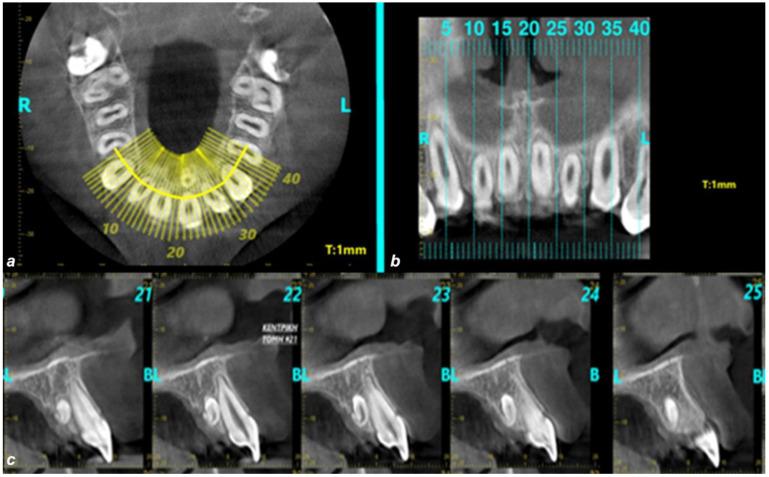

The aim of this retrospective study was to investigate the supernumerary teeth located in the anterior region of the maxilla of non-syndromic Greek children and adolescents, as well as their possible correlation with demographic characteristics and radiographic findings. The study sample comprised cone-beam computed tomography (CBCT) scans from 224 children and adolescents aged up to 18 years. The following parameters were studied: location of supernumerary teeth in the anterior maxillary area, their morphology, their relationship to adjacent anatomical structures and adjacent teeth, and potential implications. Out of the 224 cases 26 (11.6%) presented supernumerary teeth. There was higher prevalence in males than females (61.5% versus 38.5%, respectively). Among the 26 participants diagnosed with supernumerary teeth, one supernumerary tooth was found in 80.8% of children/adolescents, while 19.2% had two supernumerary teeth. The vast majority of supernumerary teeth were impacted (92.3%), and their morphology in 57.7% of cases was conical. A total of 38.5% of cases had normal orientation, 26.9% inverted orientation, 19.2% horizontal orientation, and 15.4% other. The localization was palatal in 84.6%, and the area of localization for 50% of cases was the midline. The prevalence of supernumerary teeth in the studied sample of Greek children and adolescents was 11.6% and tended to appear as single, impacted, conical, and with normal orientation. However, these results should be interpreted with caution, due to the limitations in the sampling strategy and the restricted generalizability of this study. The need for further research to enhance broader applicability for different populations is highlighted. These findings are instrumental for a more comprehensive understanding of the prevalence of supernumerary teeth, contributing to more accurate and individualized dental treatment planning in children and adolescents. This will help to avoid future issues in the patient's dentition.

这项回顾性研究的目的是调查非综合征性希腊儿童和青少年上颌前部区域的多生牙,以及它们与人口统计学特征和影像学表现之间的可能关联。研究样本包括224名18岁及以下儿童和青少年的锥形束计算机断层扫描(CBCT)。研究了以下参数:上颌前部区域多生牙的位置、形态、与相邻解剖结构和相邻牙齿的关系以及潜在影响。在224例病例中,26例(11.6%)出现多生牙。男性患病率高于女性(分别为61.5%和38.5%)。在26名被诊断有多生牙的参与者中,80.8%的儿童/青少年发现一颗多生牙,而19.2%有两颗多生牙。绝大多数多生牙为埋伏阻生(92.3%),57.7%的病例其形态为锥形。共有38.5%的病例方向正常,26.9%倒置,19.2%水平,15.4%为其他方向。84.6%位于腭侧,50%的病例位于中线区域。在希腊儿童和青少年的研究样本中,多生牙的患病率为11.6%,倾向于表现为单个、埋伏阻生、锥形且方向正常。然而,由于抽样策略的局限性和本研究的普遍适用性受限,这些结果应谨慎解释。强调了进一步研究以提高对不同人群更广泛适用性的必要性。这些发现有助于更全面地了解多生牙的患病率,有助于儿童和青少年更准确和个性化的牙科治疗计划。这将有助于避免患者牙列未来出现问题。